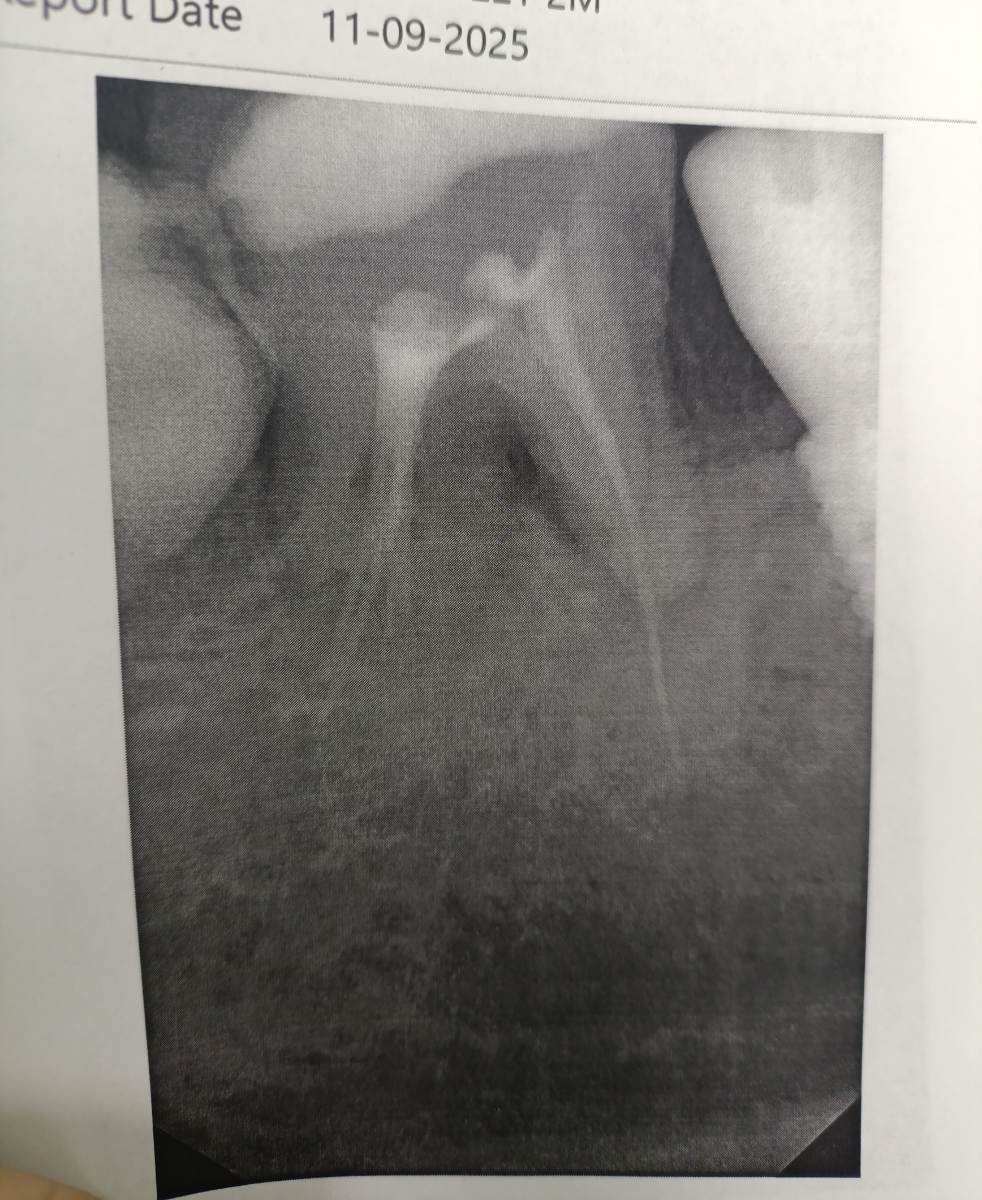

Очаг воспаления между корнями

Добрый день, был глубокий кариес у зуба, начали лечить поставили пульпит. Заложили лекарство, спустя 2 недели боли сохранялись, убрали лекарство, прочистили каналы и запломбировали. Теперь боли полностью ушли, но появляются если дать зубу нагрузку жевательную значительную. То есть если интенсивно жевать на этом зубе, в течение дня начинает нарастать чувствительность зуба (болью не совсем это можно назвать) но на следующий день после сна боль всегда проходит.

Лечение в бесплатно клинике было, поэтому сказали что зуб только удалять, так как воспаление между корнями.

Два снимка с разницей в месяц